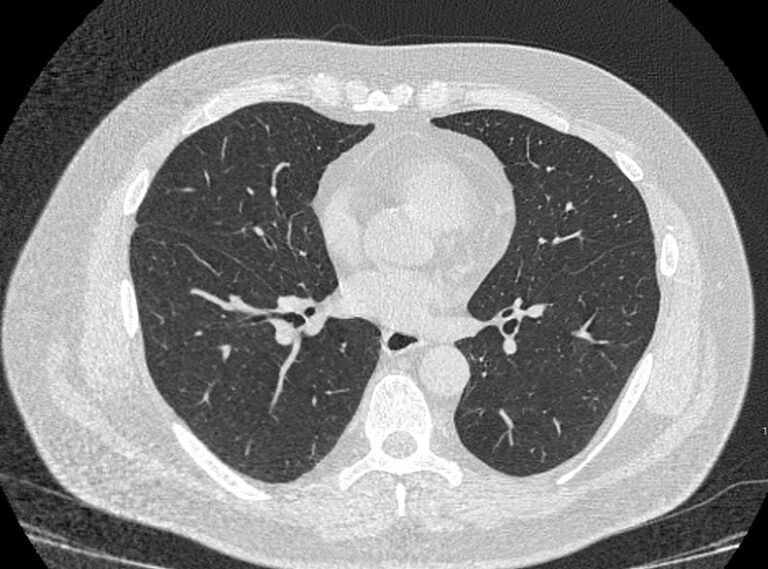

Во время исследования рентгеновская трубка томографа вращается вокруг исследуемой области и производит множество послойных снимков с шагом 0,5-1 мм. Полученные снимки поперечного сечения с помощью компьютерной программы могут быть преобразованы в 3D-изображения исследуемого органа или участка ткани. Это позволяет выявлять практически все заболевания легких на ранних стадиях и назначать своевременное лечение.

В текущей эпидемиологической обстановке КТ легких является методом выбора при диагностике новой коронавирусной инфекции ( COVID-19).

С помощью КТ можно выявить новообразования на ранней стадии и туберкулез. Также КТ легких актуальна для наблюдения за послеоперационным и дооперационным состоянием проблемного органа.